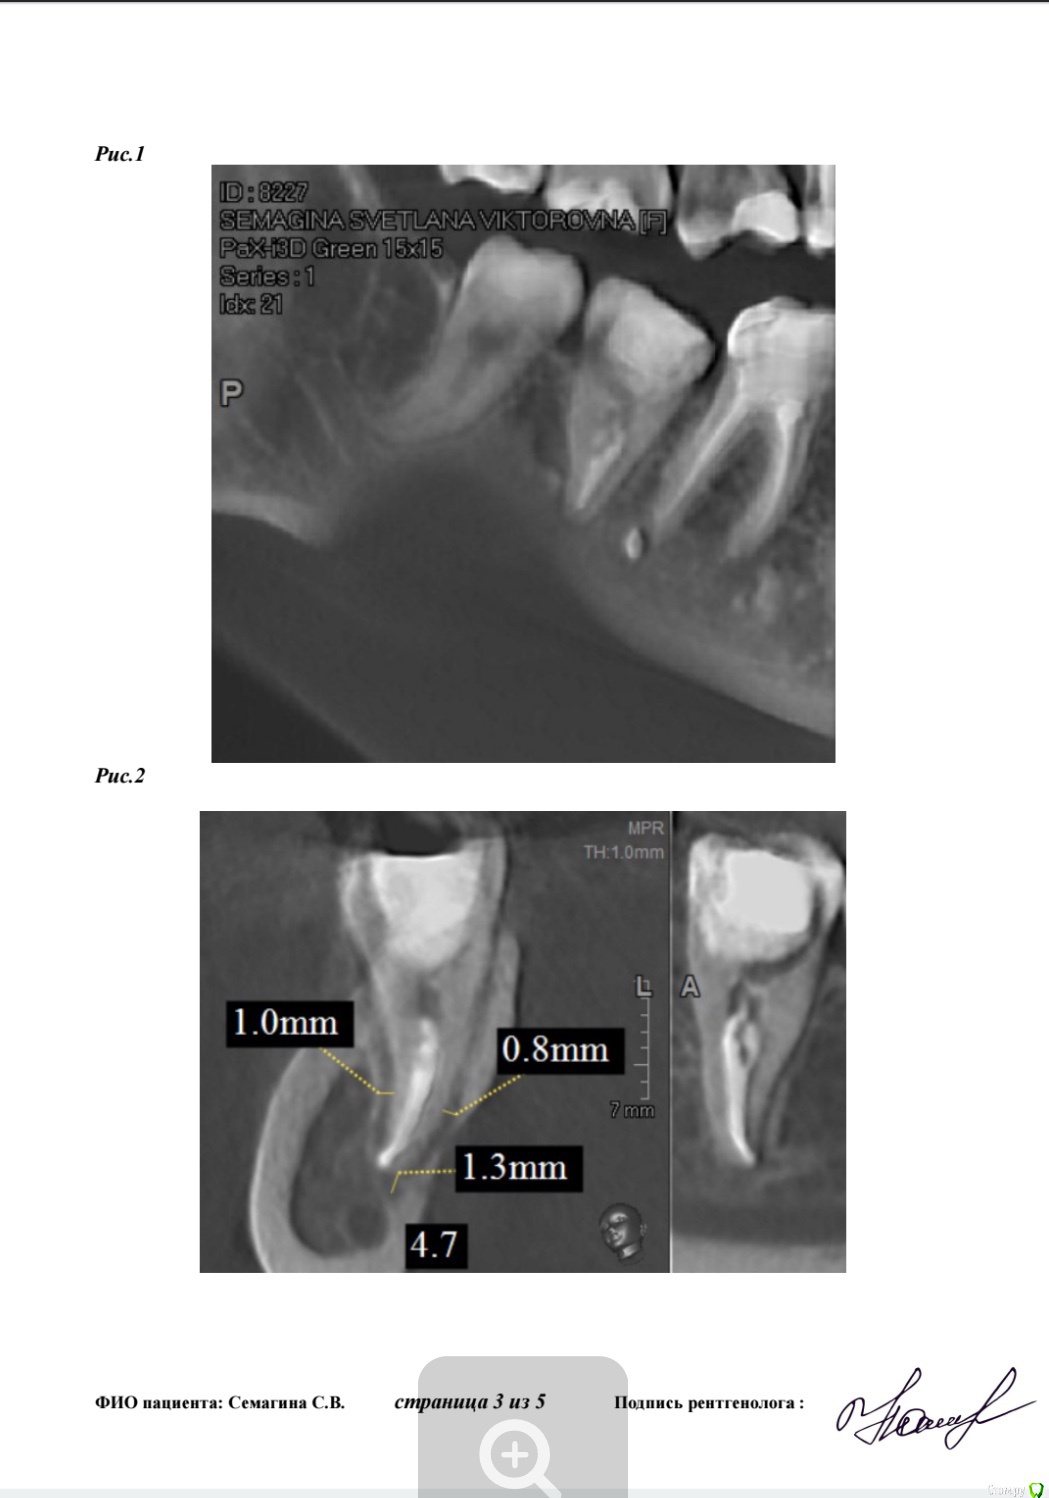

Лана-Лана Опубликовано 14 февраля, 2018 Поделиться Опубликовано 14 февраля, 2018 (изменено) Зуб семерка справа нижний, перелечивался после перидонтита... состояние такое как на кт, сам не болит но жевать невозможно, есть ли смысл перелечивать ? Очень хочу зуб сохранить... запломбированн на одну треть .. место под вкладку . На данный момент все таки раскрыли поставили метопасту. Изменено 14 февраля, 2018 пользователем Лана-Лана Ссылка на комментарий

Лана-Лана Опубликовано 15 февраля, 2018 Автор Поделиться Опубликовано 15 февраля, 2018 (изменено) Сейчас зуб в таком состоянии с метапиксом( перепутала изначально сказала метопаста), вижу темное пятно слева от зуба это что воспаление? И так же вижу слева как второй корень именно корень а не канал... он как бы чуть чуть выглядывает из за первого корня , или это наслоение какое то?. в первом корне 2 канала а может быть в другом корне тоже какой то патайной канал которого воачи не видят ? Изменено 15 февраля, 2018 пользователем Лана-Лана Ссылка на комментарий

Лана-Лана Опубликовано 17 февраля, 2018 Автор Поделиться Опубликовано 17 февраля, 2018 Зуб стал болеть с метапиксом такая давящая ноющая, припухлость не уходит! Что делать дальше? Ждать ? Сказали ходить три недели! Или пойти поменять лекарство? Уважаемые доктора посмотрите последний снимок почему лекарство не до апекса? Оно вообще как то подействует на воспаление в кости в десне? Может ли быть в таком зубе третий канал скрытый? Может какой то внутри разделяется на два? По кт может что то видно? Ссылка на комментарий